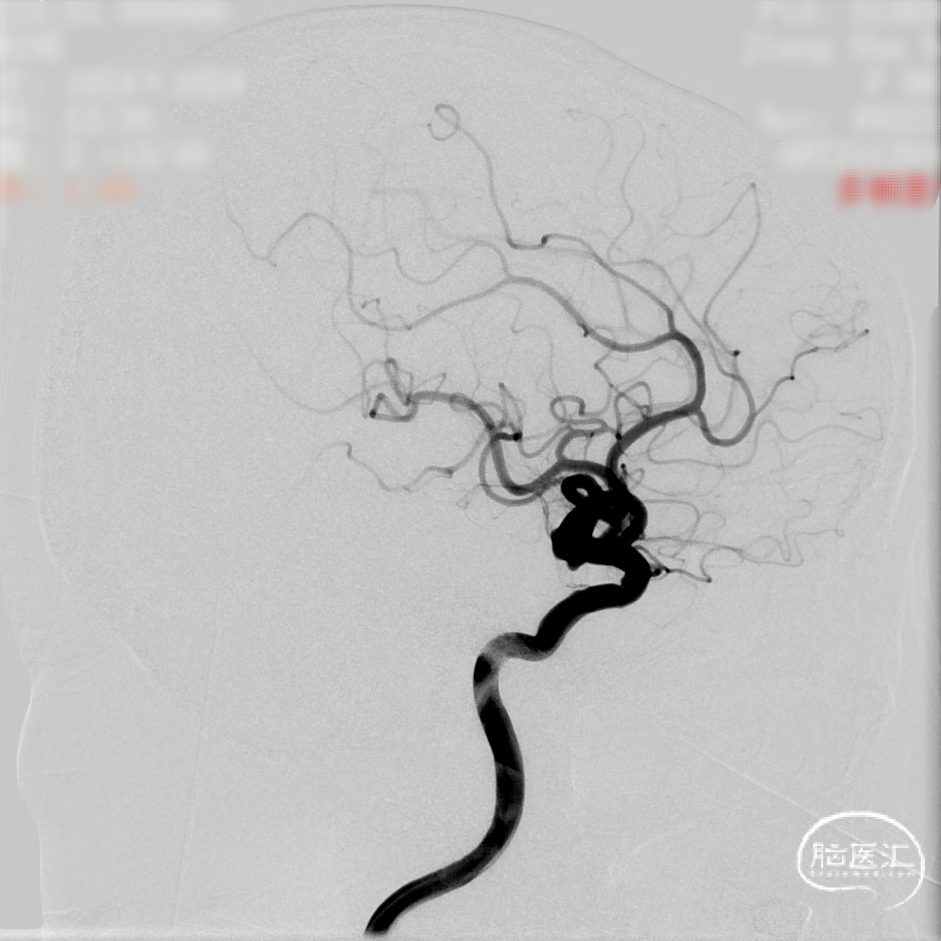

CTA:右侧颈内动脉C7段动脉瘤。

DSA造影:

工作角度: